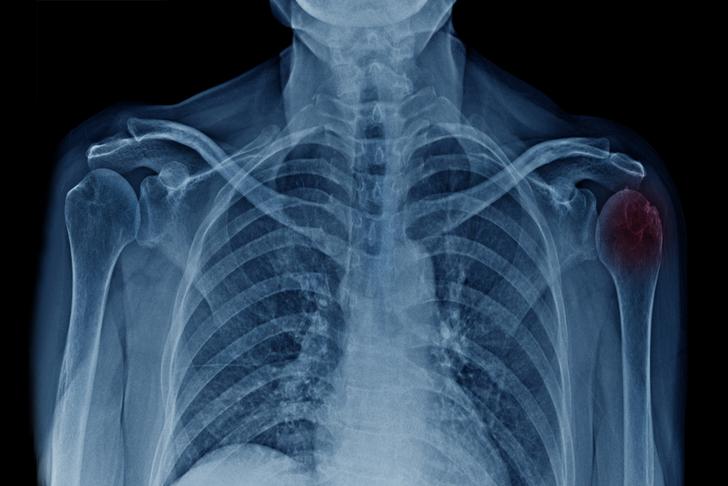

Fractures of the Proximal Humerus

A fracture of the proximal humerus, the upper part of the arm bone, can cause severe shoulder pain, swelling, and bruising [[8]]. These fractures often result from falls, sports injuries, or motor vehicle accidents.